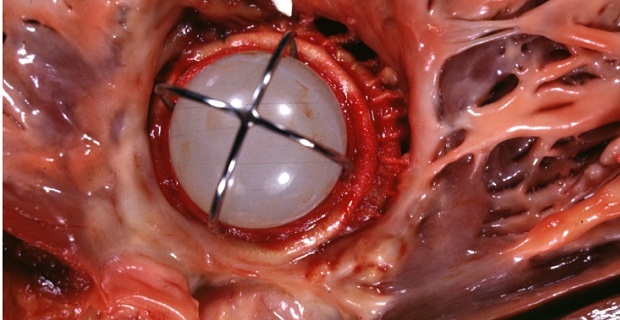

Mitral Valve Disease | Thoracic Key

Mitral Valve Disease | Thoracic Key thoracickey.com

mitral valve disease stenosis figure

Mitral Valve Disease | Circulation

Mitral Valve Disease | Circulation www.ahajournals.org

mitral